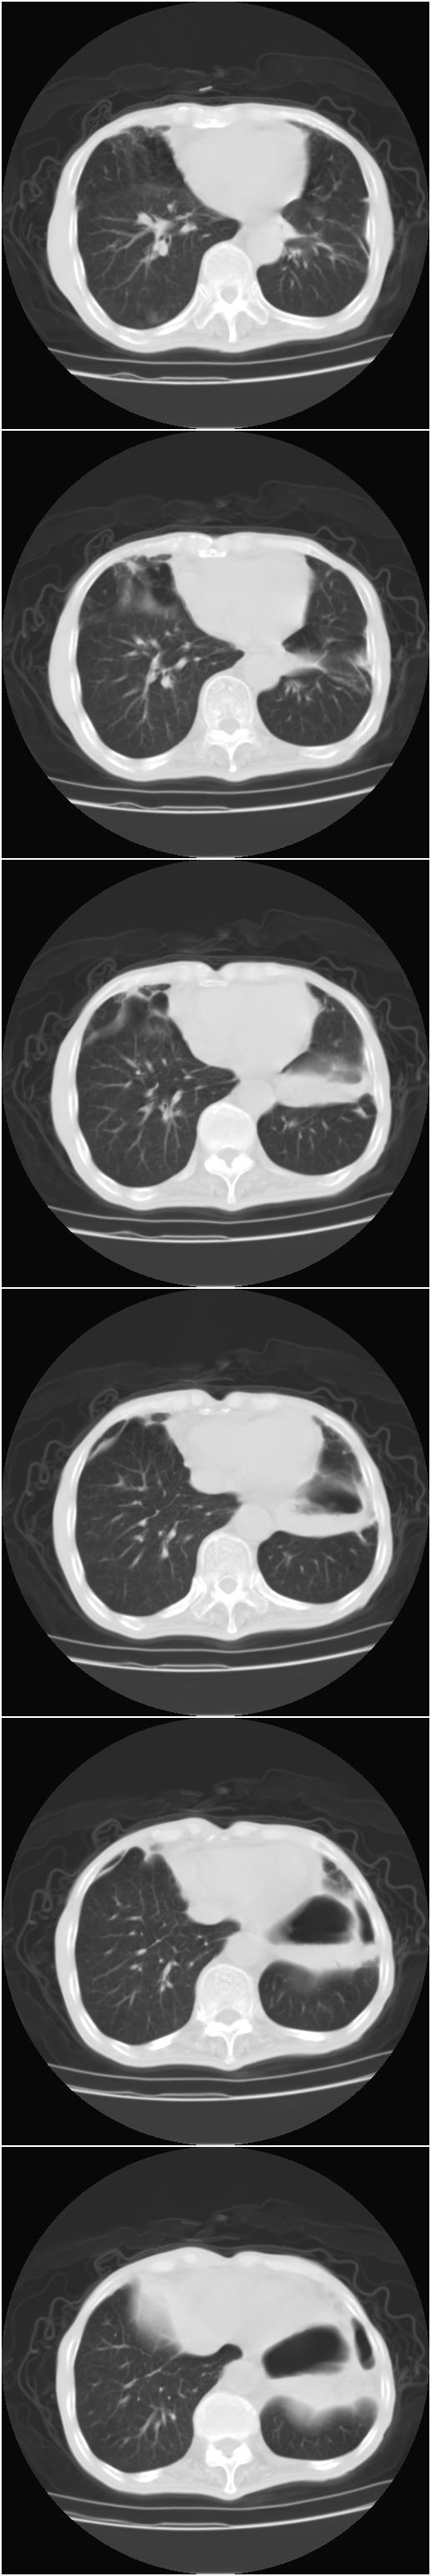

标题: CT12024:男,77岁。咳嗽两月余,气喘一月,13年前岑作贲门 [打印本页]

标题: CT12024:男,77岁。咳嗽两月余,气喘一月,13年前岑作贲门

1、右侧中心型肺癌,右肺门,纵隔淋巴结转移可能性大。

2、贲门癌术后所见。

右侧中心型肺癌,右肺门,纵隔淋巴结转移。

右中心型肺癌 纵隔淋巴结转移

右侧中央型肺癌伴右肺门及纵隔淋巴结转移.

1 右肺中心型肺癌伴右肺门及纵隔淋巴结转移.

2  左肺贲门癌术后改变.

1)考虑为:右侧中心型肺癌并右肺门及纵隔淋巴结转移。2)贲门癌术后改变。